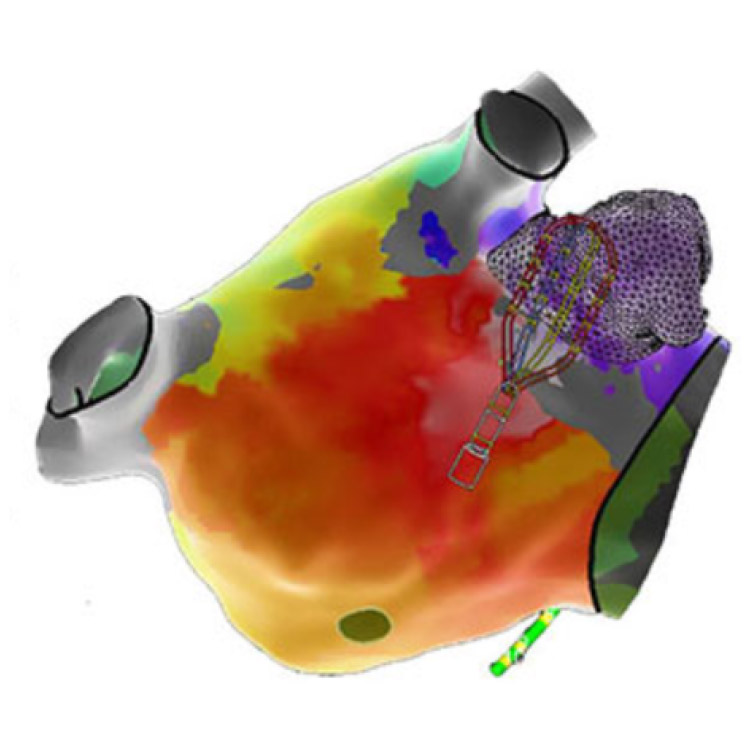

また、CARTO・EnSiteなどの3次元マッピングシステムを使用し、安全かつ高精度な治療を行っています。

3次元マッピングシステム

心臓CTや心腔内エコーで得られた心臓の立体的な画像と可視化された電気信号を正確に重ね合わせます。CARTO、EnSiteなどの3次元マッピングシステムを用いることにより治療成績および安全性の向上が得られます。

- CARTO

- EnSite